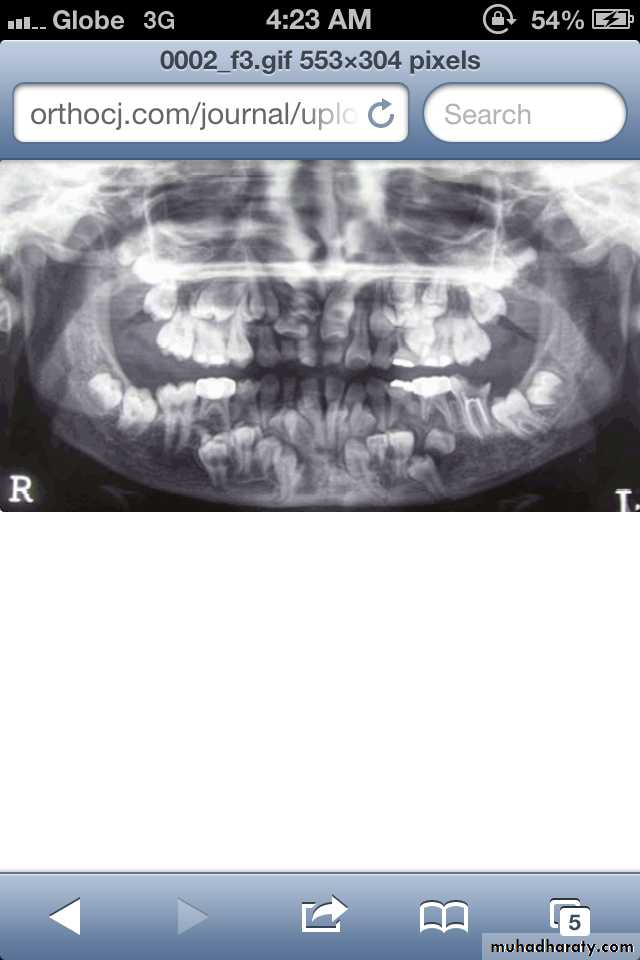

Hypodontia

Oligodontia

Anadontia

Developmental absence of all maxillary premolars and both mandibular second premolars. Note the retention of the maxillary primary canine as a result of the posterior position of the maxillary permanent canine.